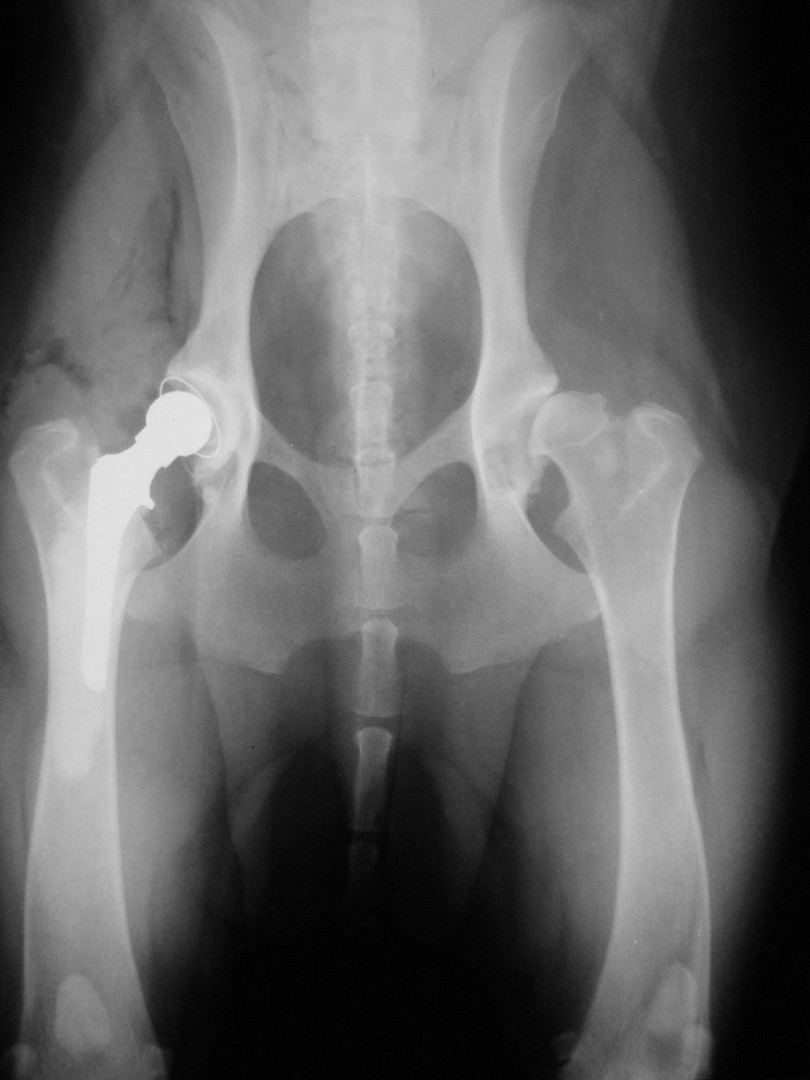

Teljes csípőízületi protézis

Bár a csípőízület megbetegedéseiről – mint a leggyakrabban tárgyalt ortopédiai megbetegedésről- első körben nem szerettem volna szólni, mégis megteszem, mert 2010. májusában egy hosszabb egyeztetést és szervezést követően beültettük az első teljes csípőízületi protézist…

Az első műtét remekül sikerült és Connor, a skót juhász kutya megkapta a bal oldali új csípőízületét. A 7 napi kórházi tartás is problémamentesen zajlott és a varratszedés idejére a műtött végtag terhelése gyakorlatilag hibátlan volt. Az 1 hónapos és a 3 hónapos kontroll RTG vizsgálatokon sem jelentkezett szövődményre utaló jel, az 1 éves postoperatív időszakban már csak az látszott, hogy a műtött lábát jobban terheli, mint a nem operált végtagot. Így 2011. júniusában – immár sokadik csípőízületi protézis műtétként- a jobb oldali csípőízületét is megoperáltuk. Connor gyakorlatilag azóta teljes életet él és vidáman játszik társaival, még birkákat is terel…A majd két éves, a protetizálás során szerzett tapasztalatok azonban nálunk is hozzák a szakirodalomban leírt szövődményi lehetőségeket és arányokat. Leggyakrabban a beültetett protézis ficamával találkoztunk, de akadt sajnos kilökődési reakció is. Ezen problémák – az előzetes tájékoztatás ellenére is- mindig váratlanul érik a tulajdonost és az állatorvost egyaránt. Megoldásuk szinte kizárólag műtéti, ami újabb kockázatot, újabb fizikai és anyagi áldozatot jelent.